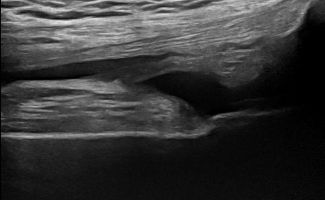

Άρθρωση και Θύλακοι Γόνατος

Η παρουσία συλλογής υγρού, θυλακίτιδας ή υμενίτιδας που ανιχνεύεται με το Υπερηχογράφημα Γόνατος μπορεί να σχετίζεται με ρευματολογική νόσο, όπως:

- Οστεοαρθρίτιδα